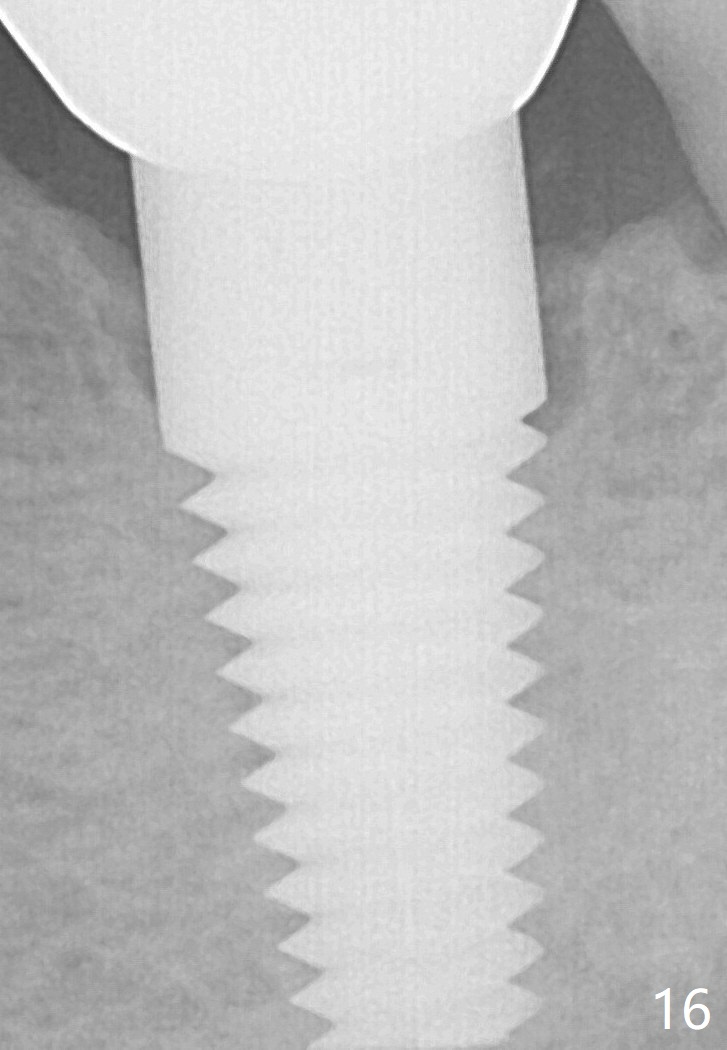

No bone loss is noticed 26 (Fig.15) or 38 (Fig.16) months post cementation.